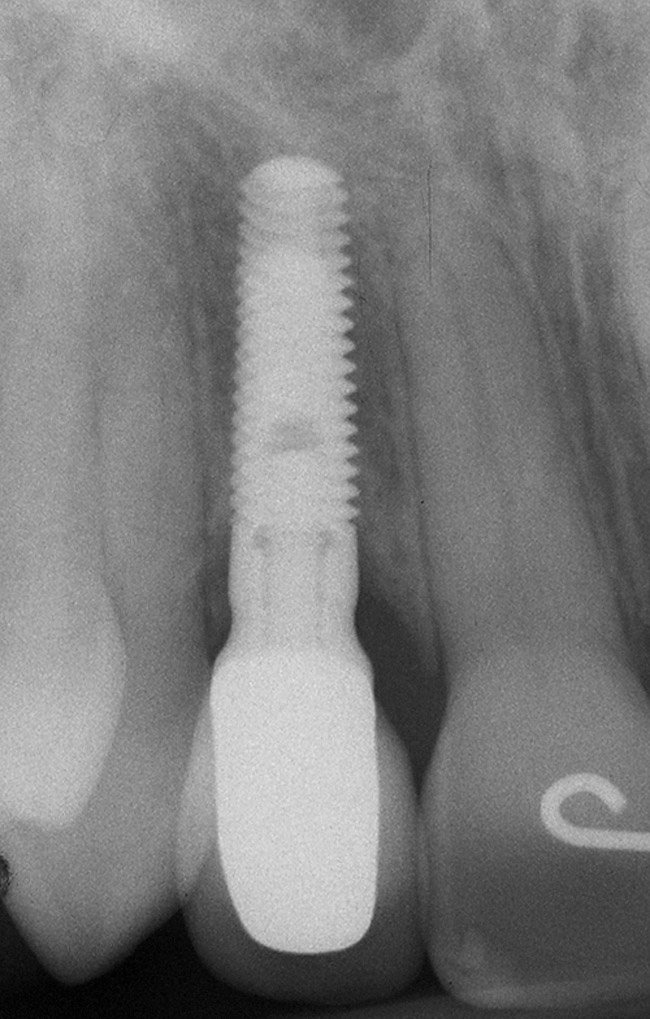

Figure 5h  Postoperative radiographs.

Figure 5h

Figure 5g  Postoperative radiographs.

Figure 5i